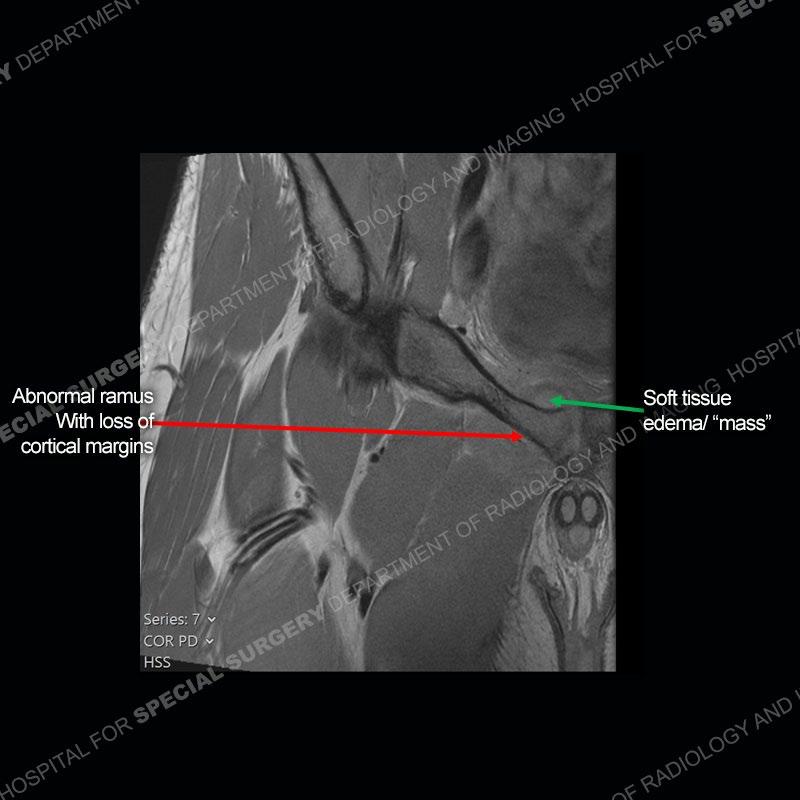

Radiographs did not demonstrate any clear abnormality. The MRI shows markedly abnormal signal of the right superior pubic ramus and abnormal signal/”mass” extending into the adjacent soft tissue. The inferior articular surface of the ramus showed what was thought to be bony destruction. CT examination shows a destructive process of the right superior pubic ramus.

Subsequent MRI in a very short time interval shows markedly increased abnormality of the ramus and increased edema and “mass” of the soft tissue. Post contrast imaging shows multiple, rim enhancing collections of the soft tissue and similar albeit less conspicuous enhancing collection of the ramus.